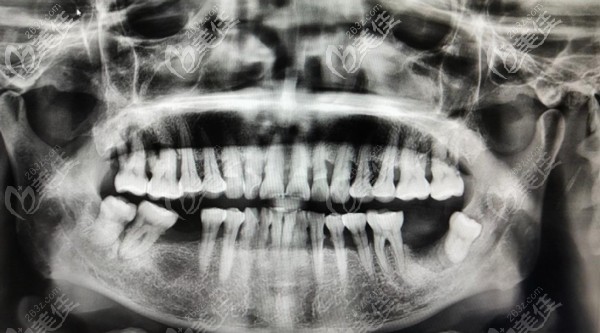

我的父親今年60歲,打我記事起一直從事的是建筑行業(yè),所以有長期吸煙的習(xí)慣,自去年開始他的牙齒慢慢開始松動(dòng)甚至開始脫落,后來到口腔醫(yī)院檢查才知道是常年吸煙導(dǎo)致的牙齦萎縮繼而引起的滿口牙松動(dòng)。

通過咨詢我們了解通過種植牙齒是可以恢復(fù)基本咀嚼功能的,但由于父親牙槽骨萎縮比較厲害,所以需要先進(jìn)行植骨,之后4-6月后才能種牙,而且種牙后不能即刻飲食,需要再等3-6個(gè)月后才能裝牙冠。